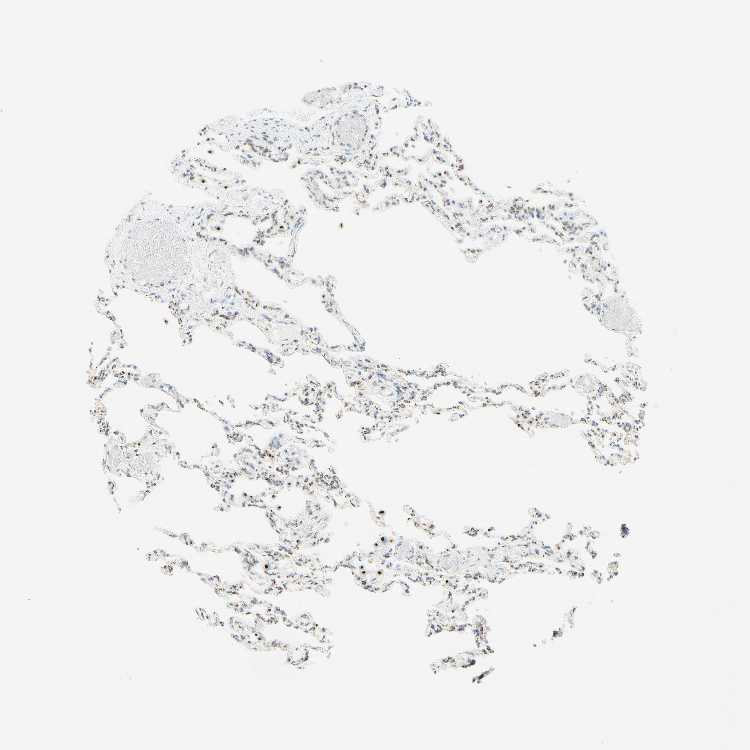

LUNG - Antibody stainingi

Antibody staining in the annotated cell types in the current human tissue is reported as not detected, low, medium, or high, based on conventional immunohistochemistry profiling in selected tissues. This score is based on the combination of the staining intensity and fraction of stained cells.

Each image is clickable and will lead to virtual microscopy that enables deeper exploration of all samples and also displays staining intensity scores, fraction scores and subcellular localization as well as patient and tissue information for each sample.

Antibody HPA011008Antibody HPA011555

Alveolar cells High-

Alveolar cells type I -High

Alveolar cells type II -High

Endothelial cells -Not detected

Macrophages HighHigh